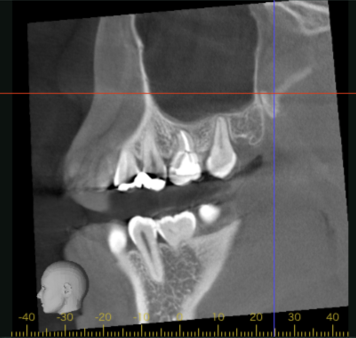

移植12ヶ月後のCT画像①

移植12ヶ月後のCT画像②

移植12ヶ月後。CT画像では、歯根周囲に骨が形成されていることが確認できる。

患者さまは特に違和感なく快適に過ごされているとのこと。